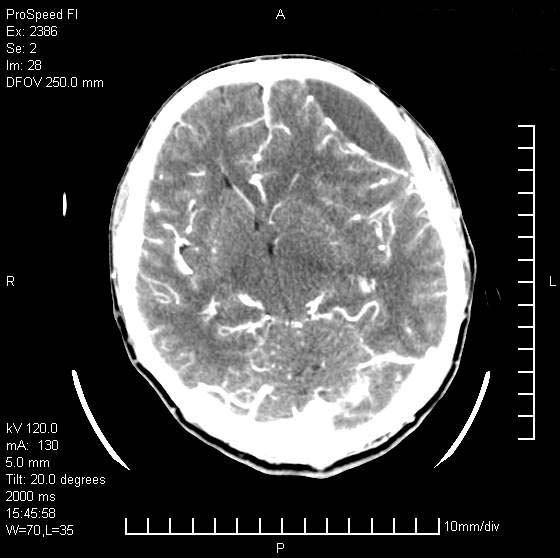

以下是引用天南地北在2007-9-19 18:43:00的发言:[br]典型慢性硬膜外血肿[br][br][本贴已被 天南地北 于 2007-9-19 18:44:11 修改过]

以下是引用曼一拍在2007-9-20 11:06:00的发言:[br]支持慢性硬膜下血肿.[br]慢性硬膜下积液:血肿有包膜,ct值稍高于脑脊液,增强可有染色。不典型者血肿可多呈梭形.是硬脑膜与蛛网膜之间的潜在腔隙内的血肿。[br]鉴别:[br]1\\硬膜外血肿:是颅脑外伤后脑膜或板障内血管破裂,血液在颅骨与硬膜之间积聚所致.通常是脑膜动脉破裂,也可因静脉窦破裂或颅骨的板障静脉出血,发生于外伤的着力部,常与颅骨骨折并存。脑膜动脉出血则急,若是板障静脉出血在则可有慢性。[br]2\\硬膜下积液:(硬膜下水瘤)[br]是由于蛛网膜破裂,脑脊液经蛛网膜破口进入硬膜下腔不能回流。或水肿阻塞而形成。[br]ct表现:颅骨内板下方新月形低密度区近似脑脊液密度;占位效应清,周围无脑水肿。[br]